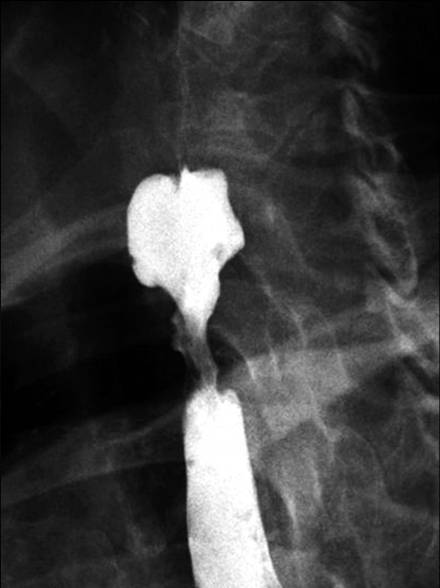

上食管括约肌支撑架占全部食道癌的7~10%,上食管括约肌附近支撑架(Stents near the upper esophageal sphincter)植入困难,曾被列入禁忌症。主要风险包括支撑架植入后穿孔、吸入性肺炎,向近端移位,不能忍受的疼痛和不能忍受的球状异物感(globus sensation)[1,2]。

姑息性放疗为传统治疗,但尝试在这一部位植入支撑架正在逐渐地增加。最大一组颈段食管狭窄支撑架植入是44例。内窥镜/透视联合引导对于精确定位支撑架近端刚好位于上食道括约肌下非常重要。5%~15%有球状异物感,但没有病人需要取出支撑架。

为了减少食道支撑架在食道括约肌水平的异物感,专门设计的颈段食管支撑架是在上端喇叭口仅有7mm[3]

除了将喇叭口长度减短,另一项策略是减少颈部食管狭窄支撑架的直径即10mm、12mm和14mm直径的食道支撑架,上端喇叭口直径分别为12mm,14mm和16mm[4。